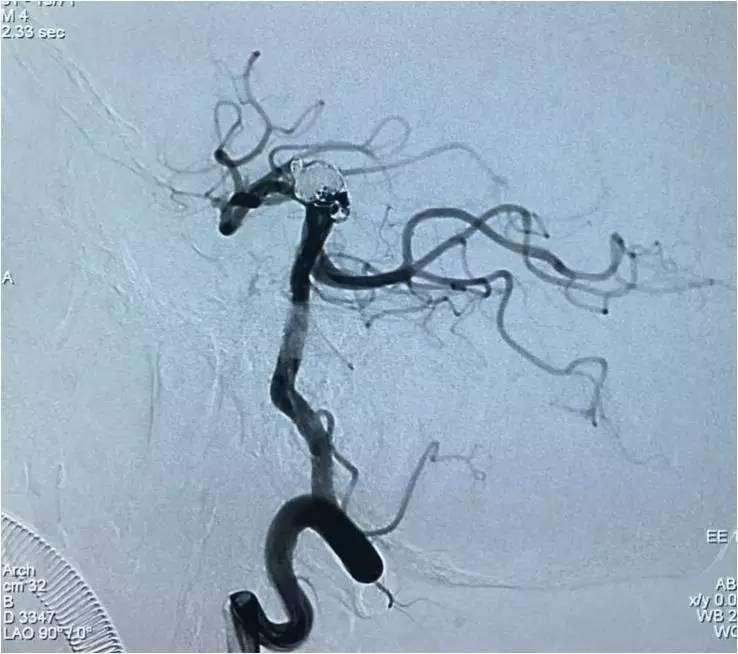

下面是术后各个角度的左椎动脉造影,可见基底动脉顶端动脉瘤和左小脑上动脉瘤完全栓塞,载瘤动脉畅通。基底动脉顶端动脉瘤的子瘤终于被消灭。

▼侧位。

▼正位汤46度。